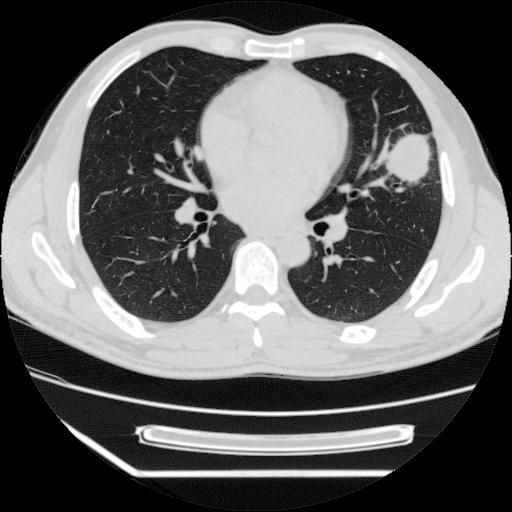

男,38岁,于2009年8月9日晚突发左侧胸痛,今x线提示左下肺阴影,为了明显确诊断,行ct检查,

病灶发生在下叶,密度均匀,边缘模糊、毛糙,周围血管纹理增强扭曲改变,靠近胸膜处病灶胸膜反应明显。

支持考虑---球形肺炎。

左肺舌叶病变。主体病灶呈类圆形中心密度低,成液化趋势周边班片影分布

考虑肺脓肿

虽然实验室检查支持炎性病变,且病变内有坏死改变(中央呈大片状低密度影),但仍不能掉以轻心,鳞癌也可以有这种影像改变。